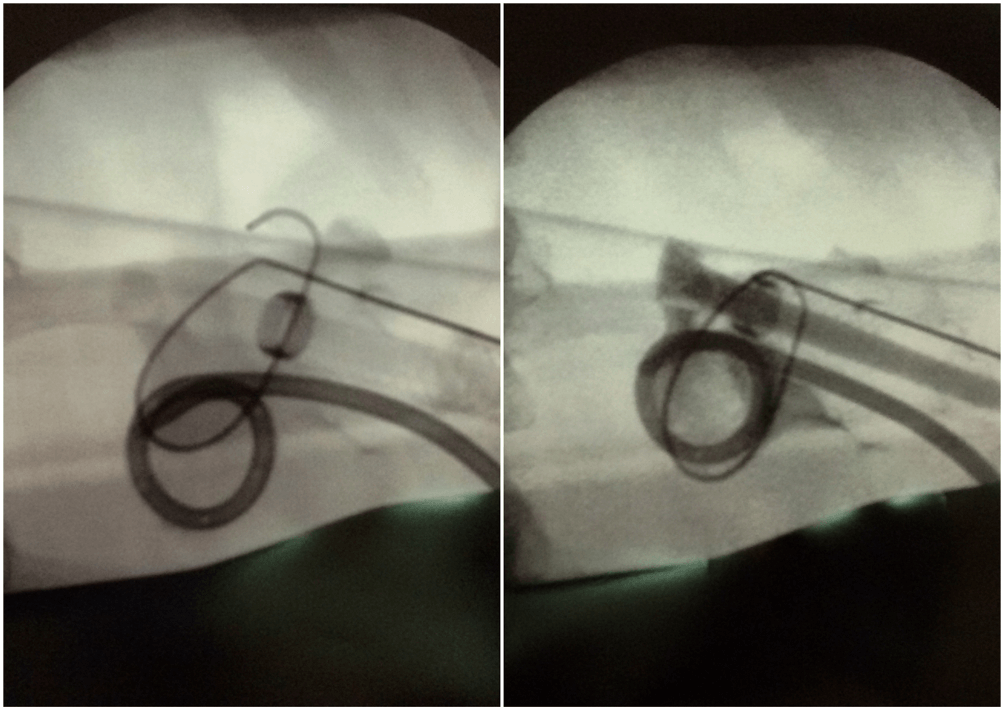

Radioczuły znacznik w proksymalnej części protezy pomaga ustabilizować jej pozycję tak, aby osłona PTFE była objęta miąższem nerki i nie wnikała do UKM co zapobiega inkrustacjom a jednocześnie miąższ nerki stabilizuje protezę (ryc.4)

Rycina 4: Śródoperacyjne zdjęcia RTG w trakcie implantacji protezy — po lewej widoczna proteza Detour powyżej drenu nefrostomijnego. Widoczny jest radioczuły pierścień (strzałka) markujący położenie punktu granicznego między częścią wewnętrzną i zewnętrzną końca nerkowego protezy. Po prawej moment podawania kontrastu przez protezę — widoczna oznaczone strzałką zakontrastowane światło protezy (17F).